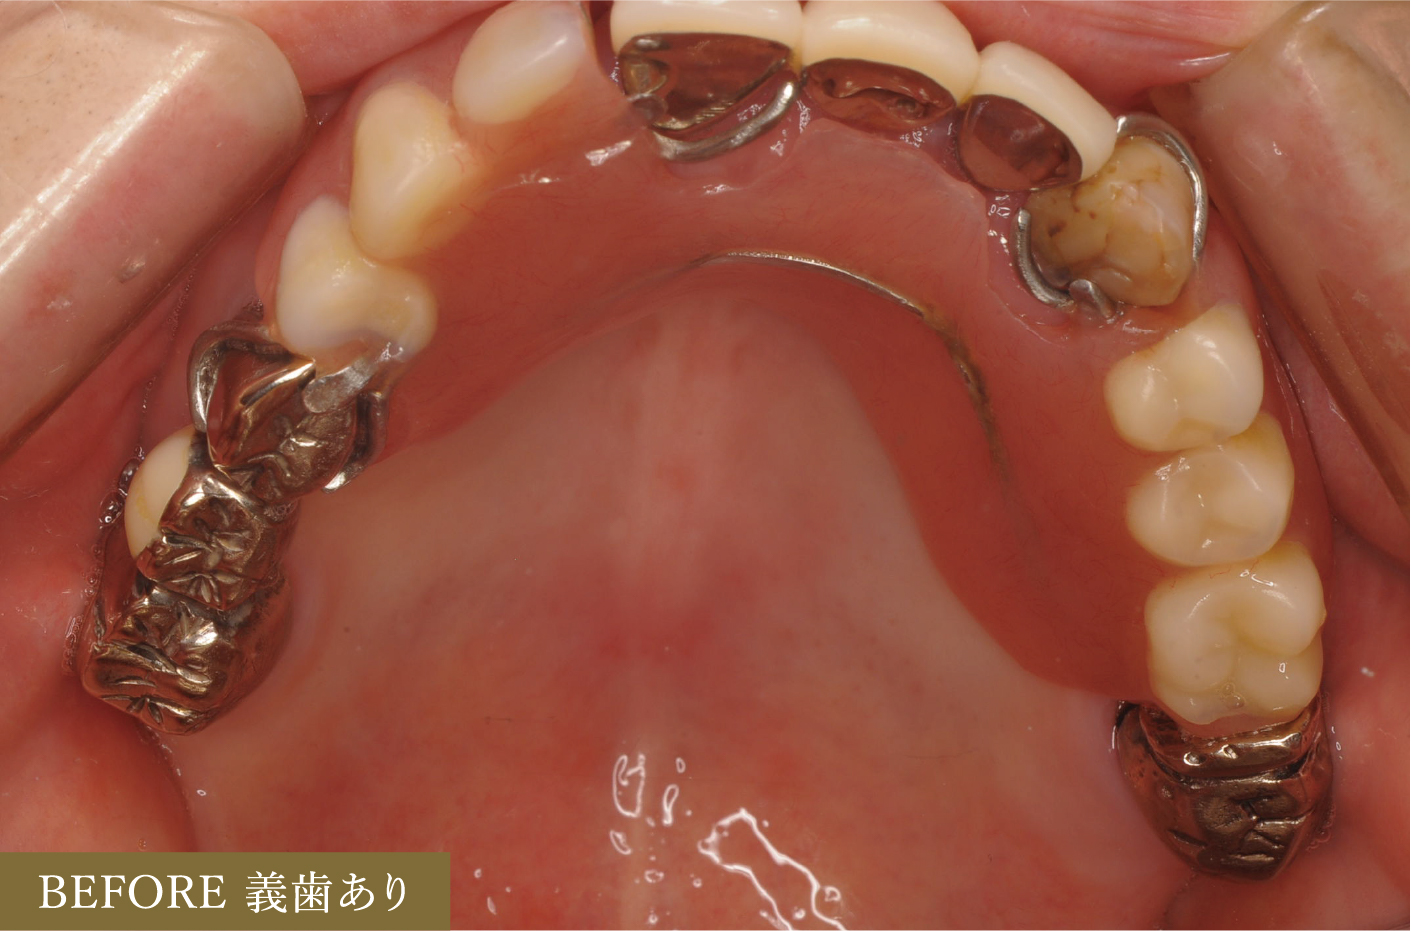

■術前術後の口腔内写真(義歯有)

この症例では

残存している歯(15本)全ての治療が必要でした。

上顎では左上3以外すべての歯に根管治療を行いました。

左上7にはソフトアタッチメント、左上4・右上5,7にはコーピング(歯に装着する金属のキャップ)、左上1,2,3・右上1にはレスト(義歯の沈下を防ぐための維持装置)を用いてスマートデンチャーを作成。

下顎では左下3・右下3,4に根管治療を行い、その後にソフトアタッチメント

左下1,2・右下1,2には虫歯の処置後CR充填を行い、その後左下1,2にはレストを用いてスマートデンチャーを作成。

上記の治療を行ったことにより、見た目と機能・長期安定性を兼ね備えた義歯を作ることができました。